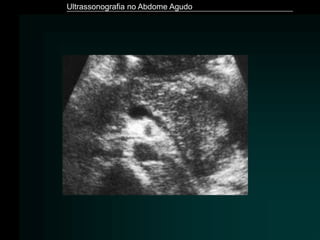

• Ultrassonografia - Fase inicial

» Imagem de adição hipoecóica – divertículo

» halo hiperecóico – processo inflamatório da gordura

adjacente

Diverticulite

• Ultrassonografia - Fase avançada

» Coleção pericólica, habitualmente com ar

» Espessamento das paredes do cólon

» Perda de definição das camadas do cólon